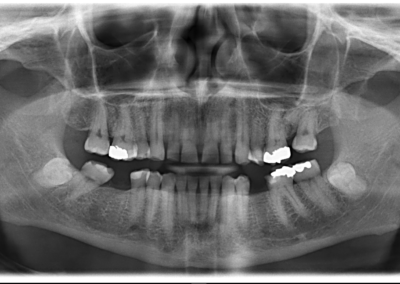

We start with a comprehensive full mouth examination, digital X-rays, a dental 3D(CBCT) scan and Trios5 Scan. The scanned images provide high-resolution images in a three dimensional plane. We use these images and scans for precise treatment planning.